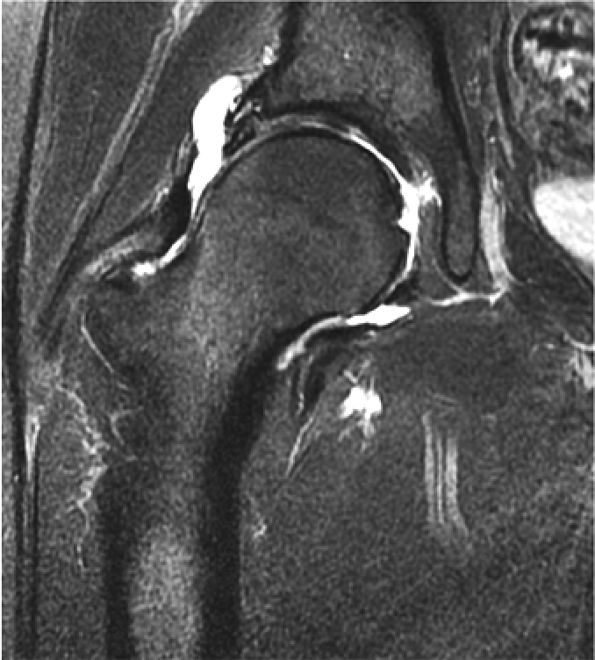

Degenerative arthritis of the right hip, with severe anterior superior chondral loss, anterior and superior labral tearing, an adjacent large paralabral cyst, and subchondral cystic changes involving the anterior acetabulum

-

Dysplastic bump in the anterolateral femoral head-neck junction associated with cam-type femoroacetabular impingement

No evidence of avascular necrosis